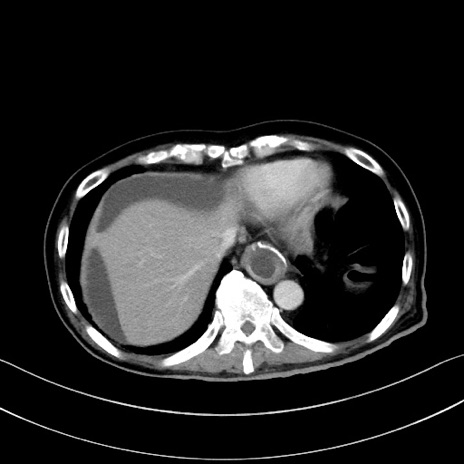

症例28(横断像)

【症例】60歳代男性

【主訴】嘔吐

【現病歴】胃癌にて胃全摘後。食思不振が悪化し、夜中に嘔吐することがある。

【既往歴】胃癌、胃全摘、脾摘、胆摘後

【データ】WBC 5900、CRP 10.56